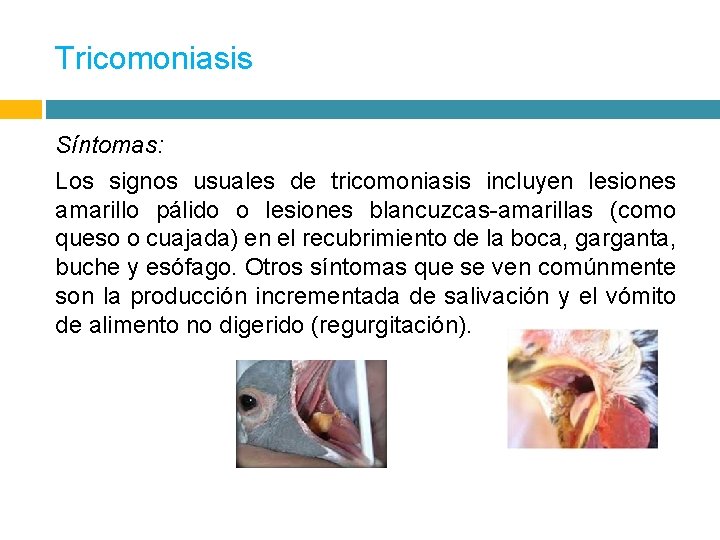

Tricomoniasis Síntomas: Los signos usuales de tricomoniasis incluyen lesiones amarillo pálido o lesiones blancuzcas-amarillas (como queso o cuajada) en el recubrimiento de la boca, garganta, buche y esófago. Otros síntomas que se ven comúnmente son la producción incrementada de salivación y el vómito de alimento no digerido (regurgitación).